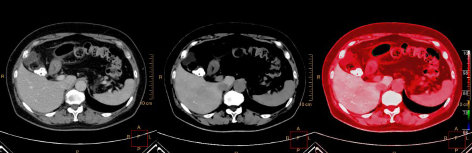

スペクトラルイメージングでは,仮想単色X線画像,ヨード密度画像,実効原子番号画像など,さまざまな情報を持った画像取得が可能であり,これらのマルチコントラストを用いた画像診断が新たな臨床的価値を生み出している。たとえば腎機能が低下した患者さんへの検査では造影剤腎症のリスクを伴うため造影剤の使用が制限されてしまう状況があり,画像診断のひとつの課題とされていた。しかし,スペクトラルイメージングの仮想単色X線画像は,少量の造影剤投与でも画像コントラストを向上させることが可能であるため,腎機能低下患者様における診断に貢献している。また,従来CT装置は形態情報とCT値が画像診断の要であるため,ビームハードニング,各種アーチファクトの影響によりこれらの情報の信頼性が揺らぎ,結果としてCTのみでは十分な診断に至る情報を得ることができず,診断確定のために他モダリティも含めた追加検査が必要となるケースも存在していた。しかしヨード密度や実効原子番号を用いた定量評価により,CT値だけでは判別がつきにくい病変や組織がより明確に診断できるようになった。

従来のワークフローを変えることなく,課題と考えられていた症例にもスペクトラルイメージングが答えを提示することで,最初に行うCT検査が最善の選択となる可能性が高まっている。